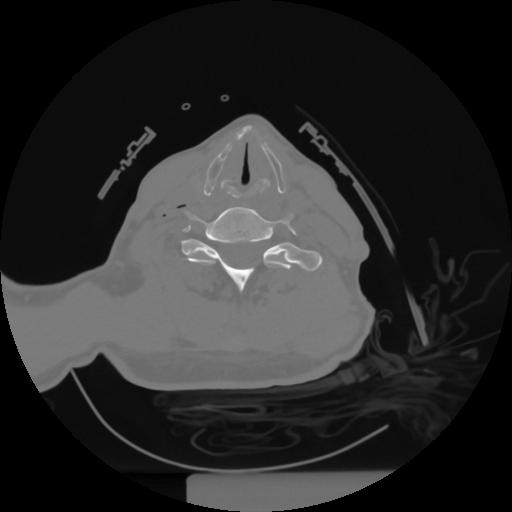

12 P.BLANDAS,,Vol,0.5,P.BLANDAS,,